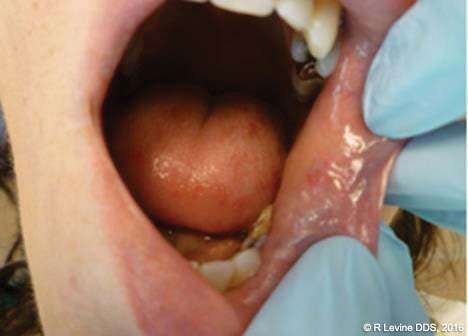

Figures 4A-4B, 5A-5B, 6A-6C, 7B-7C, and 8A demonstrate the enhanced hemostasis ensured by the LightScalpel CO2 laser. In Case 2, the patient had the vestibular extension procedure performed, and the hemorrhage was very well controlled, enabling the clinician with utmost precision. In Case 3, the bloodless excisional biopsy of fibroma was performed. Case 4 is a stage II implant uncovering procedure. This surgery requires both special accuracy and the well-controlled depth of laser energy penetration as well as enhanced hemostasis. No blood was present at any point. The implant was uncovered in approximately 30 seconds. In connection with implant uncovering, it should be mentioned that the recent study on the 10,600 nm CO2 laser removal of biofilm from titanium implant surfaces[11] reported that this laser wavelength does not affect titanium or titanium oxide (most common implant materials) and is therefore safe to use around implants. Case 5 shows a LightScalpel CO2 laser lingual frenectomy in a 7-year-old patient. Surgery is performed in a highly vascularized area where bleeding was well controlled. Finally, Case 6 is the ablation of the inflamed operculum. Figure 8A demonstrates the immediately postoperative view with excellent hemostasis.

Similar to its effect on smaller blood vessels, the CO2 laser coagulates lymphatic vessels on the margins of the incision, which results in minimal postoperative swelling and edema, and ultimately, improved, less painful healing. Lymphatic vessels regenerate successively in approximately 8 to 10 days after capillary-vessel proliferation.[12]

Among the most prominent benefits of CO2 laser treatment are minimized wound contraction and scarring.[10,13-16] Healing of CO2 laser-irradiated wounds is characterized by a more prominent fibroblastic proliferation, with young fibroblasts actively producing collagen. Compared to scalpel wounds, CO2 laser-induced wounds contain only a small number of myofibroblasts (cells responsible for wound contraction).[16-18] According to Basu, et al.,[19] and Tambuwala, et al.,[20] healing of the CO2 laser-irradiated wounds involves the appearance of a fibroserous membrane 72 hours postoperatively. This membrane replaces the superficial necrotic layer of the laser-treated area. An epithelial covering of the wound starts to form from the periphery toward the center after two weeks and is thinner and parakeratotic in comparison with the epithelium that forms after scalpel resection. This could account for the excellent esthetic outcome of all CO2 laser treatment, with no fibrosis or scarring, and soft, pliable residual tissue.

Figures 3C (capillary hemangioma of the lip), 4C (mandibular vestibuloplasty), 5C (excisional biopsy of fibroma), and 8B-8C (operculectomy) depict beautiful healing of the CO2 laser surgical sites where the wound was left to heal by secondary intention. In the case of capillary hemangioma, the lack of scarring was important for esthetic reasons; in the case of vestibuloplasty, the absence of scarring was significant to preserve functionality; in the case of fibroma excision, smooth tissue ensured that the patient would not continue check biting and that the lesion would not reoccur.